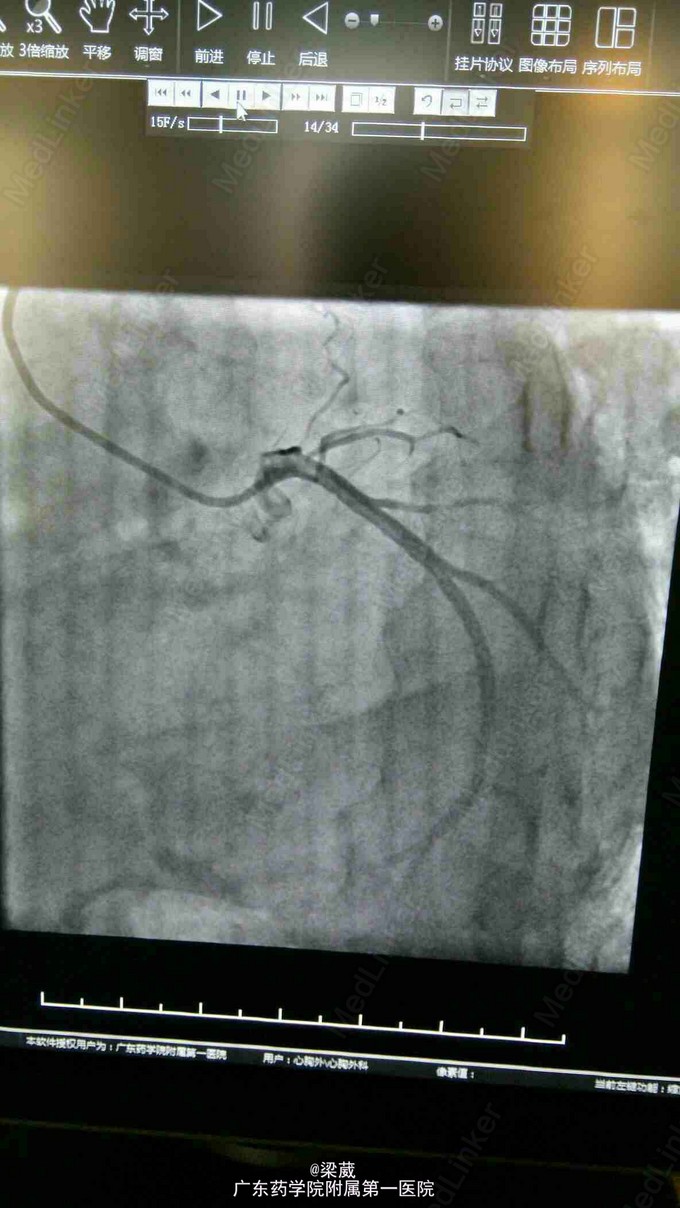

血压:131/65mmHg。神清,呼吸稍促,口唇稍苍白。双侧鼻唇沟对称,伸舌居中。双颈静脉怒张,肝颈征阴性。桶状胸,双肺呼吸音清,双肺底可闻及明显湿罗音。心前区抬举样搏动,剑突下搏动明显,心界左扩,心率121次/分,房颤律,心尖区可闻及5/6级收缩期吹风样杂音及3/6级舒张期隆隆样杂音,向左腋下传导,主动脉瓣第一听诊区可闻及3/6级收缩期喷射样杂音及2/6级舒张期哈气样杂音,三尖瓣听诊区可闻及3/6级收缩期吹风样杂音,向心底部传导,肺动脉瓣听诊区可闻及2/6级收缩期吹风样杂音,P2亢进,未闻S3、S4。腹平软,剑突下及左上腹部可有轻压痛,无反跳痛,余腹无压痛、反跳痛。未触及腹部包块,肝脏肋下2横指可及,脾脏肋下未触及,Murphy 征可疑阳性。双下肢中度浮肿。 辅助检查:肾功(三项):尿素氮 12.990(mmol/L),肌酐 126.000(umol/L);脑钠肽测定:640.700(pg/ml);胸片+颈椎片 1、风湿性心脏病联合瓣膜病变表现。心功能不全合并肺部感染。建议治疗后复查。2、慢性支气管炎、肺气肿改变。右上肺继发性肺结核(纤维化病灶为主)。3、双侧少量胸腔积液。心彩超:心脏超声, 1、二尖瓣狭窄,瓣口面积0.7cm2,伴轻中度二尖瓣反流。2、左房内附壁血栓形成。3、双房右室内径增大,左室舒张末压增高。4、肺动脉高压,肺动脉增宽,伴重度三尖瓣反流。5、少量心包积液。 2015.8.4行CAG检查,结果提示“呈左冠优势型,LAD闭塞,LCX、RCA未见明显狭窄”。

对于风湿性心脏瓣膜病变拟行换瓣手术的病人,超过50岁的患者我们常规进行冠状动脉造影检查(有的医院超过45岁即行CAG检查),以排除同时合并冠状动脉病变导致术中出现心脏灌注不足、心肌保护不佳、严重导致心肌梗塞。对于合并节段性冠状动脉狭窄(>75%)的病人同时行冠状动脉搭桥术。 但根据一些文献报道及我们自己的临床经验,风湿性心脏瓣膜病患者合并冠心病的发病几率要小于正常人群的冠心病发病率,所以虽然行CAG检查,但检出率并不高。该病例是一个重症风湿性心脏瓣膜病变患者,病程很长,年龄大,症状重,二、三尖瓣病变及伴左房巨大血栓,心脏明显扩大,CAG显示LAD近端完全闭塞,但通过右冠状动脉造影显示侧支循环代偿良好,通过侧支使LAD远端显影显示血管条件尚好、血管够粗,可行冠状动脉旁路移植术,因此拟行二尖瓣置换术+三尖瓣成形+冠状动脉旁路移植术,该手术程序复杂、时间长,加上患者本身病情严重,对于医生很有挑战性,无论手术成功与否,都能提供很多难得的经验。可惜患者放弃手术治疗。